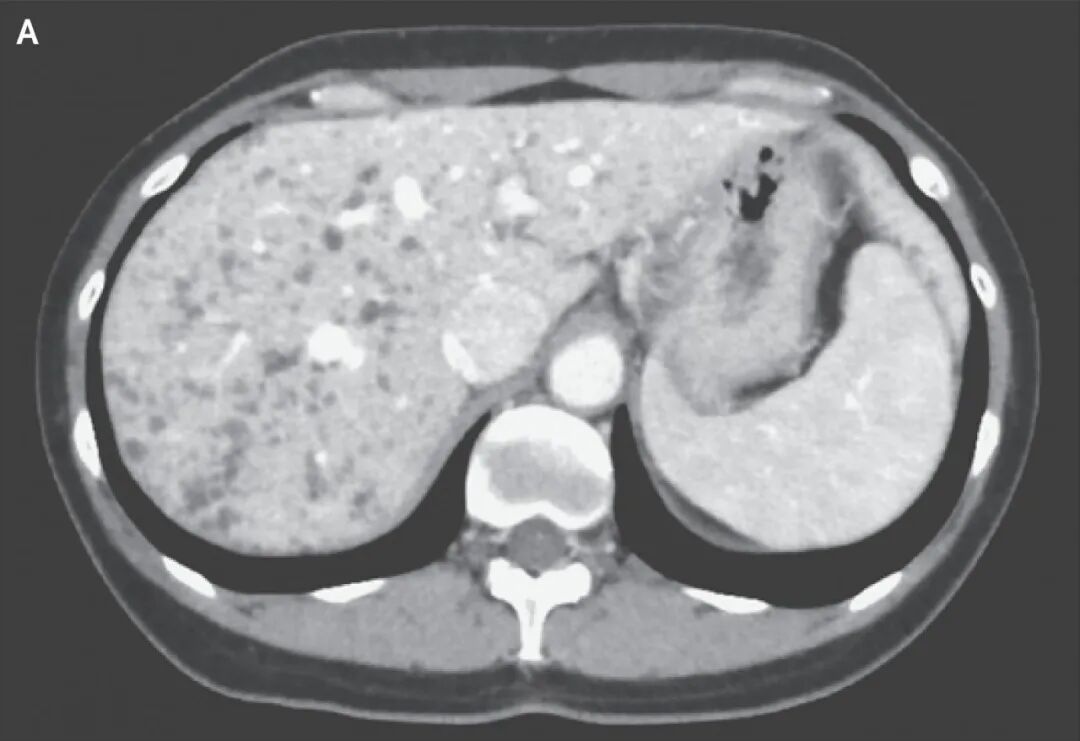

患者女,45岁,因影像学检查偶然发现肝脏多发病灶就诊。患者无相关症状,体格检查正常。实验室检查未见肝功能不全,

腹部增强CT显示遍布整个肝脏的多发低密度小结节,无强化(图A)。